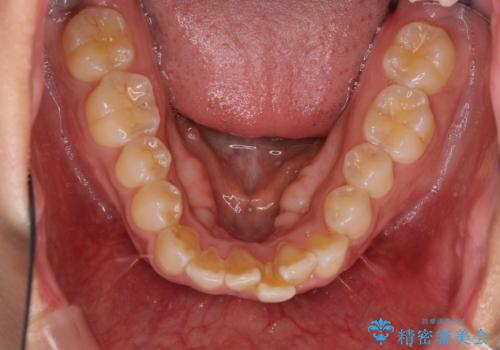

インビザラインによる狭窄歯列の拡大矯正

- 前歯のデコボコを治したいとのことで来院された患者様です。

上下顎ともに歯列全体の後方移動と側方拡大、IPR(歯と歯の間を削る)によってデコボコが解消するように設計し、インビザラインにより治療を行うこととしました。

後方移動に際し、上下の親知らずは4本とも抜歯することとしました。